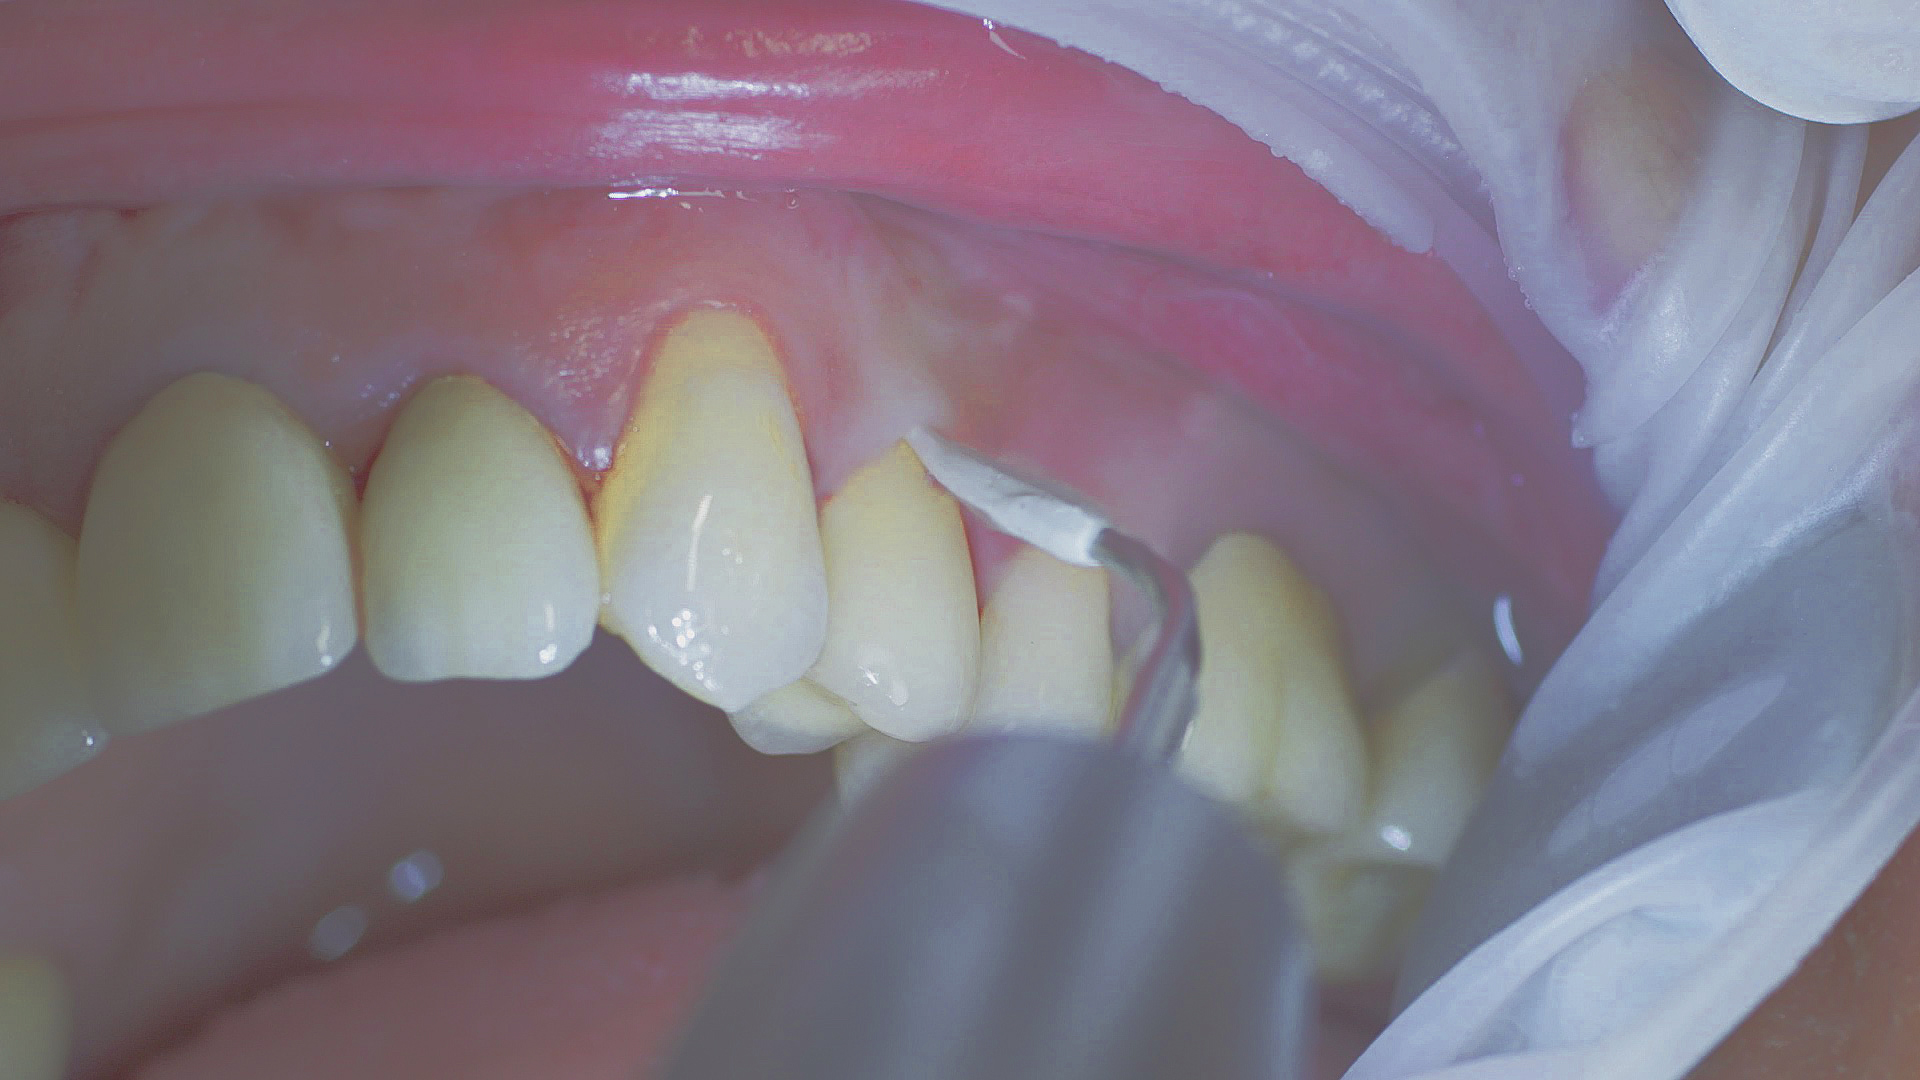

Where necessary, initial periodontal treatment is carried out. First, professional tooth cleaning establishes healthy gingival conditions. In this procedure, calculus (Fig. 1) and biofilm (Fig. 2) are removed as far as the gingival sulcus. In combination with careful instruction on oral hygiene, this gives the patient the basis for long-term freedom from inflammation.15

Removal of subgingival coatings (debridement) is carried out using sonic or ultrasonic devices and special periodontal tips as initial periodontal treatment (Fig. 3). Manual instruments can also be used. Further surgical and/or regenerative measures may be necessary, depending on the situation.